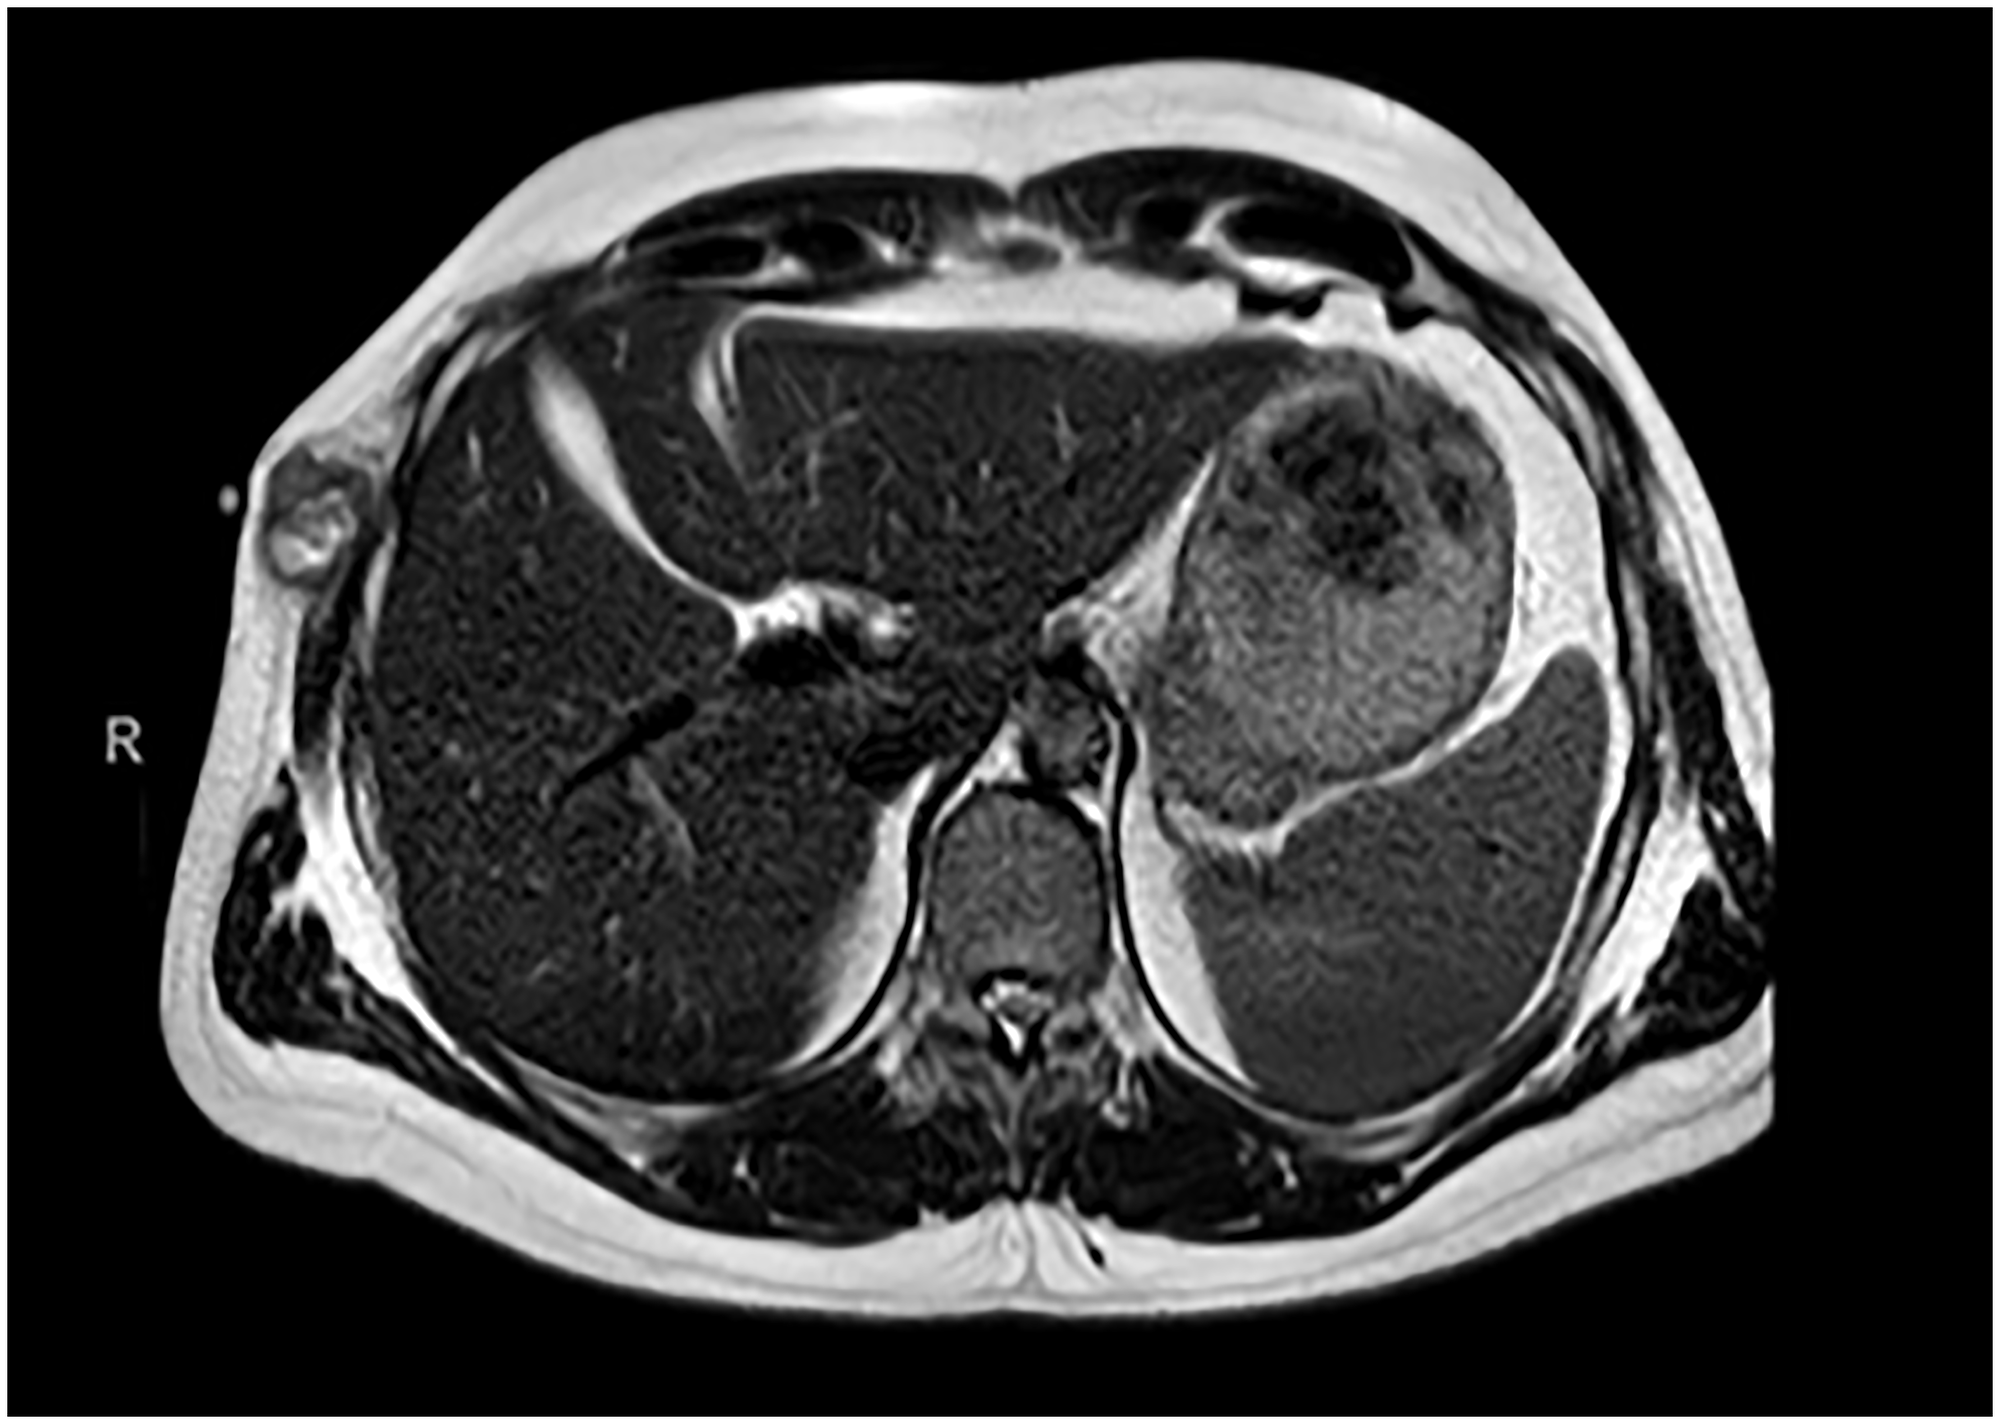

Although further surgery to widen surgical margins was recommended, there was rapid tumor growth at the surgical site, with disabling local pain. In addition, the patient presented with marked clinical deterioration consisting of progressive weight loss and profuse sweating. Chest MRI and body CT scan revealed a 6.4 cm tumor mass with local invasion of the 7th and 8th ribs, lung metastases with lung tumor embolisms, liver metastasis, and right iliac bone metastases (Figure 3).

Figure 3: Radiological imaging before treatment.

(A, B) Chest MRI 07/13/2021. Locally aggressive chest wall mass (85 × 50 x 50 mm) with intercostal extension between 7th and 9th arches and bone and muscle invasion. Fat-suppressed MRI sequence shows bone marrow edema in the contiguous 8th costal arch secondary to tumoral invasion. (C, D) CT scan 08/03/2021. Findings are suggestive of pulmonary metastatic involvement. Pulmonary tumor embolism, tree-in-bud pattern associated with a subsegmental artery in the right upper lobe.